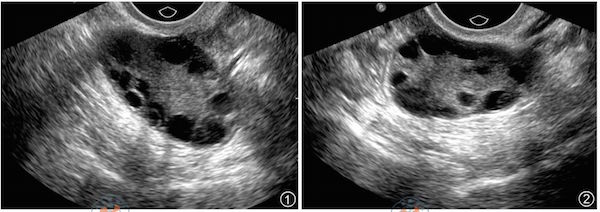

2.多囊卵巢综合征——“PCOS金标准”目前,国际上针对PCOS的诊断标准仍在不断完善,现行标准主要根据血生化和B超检查为主。血生化,主要检查体内性激素六项、抗缪勒管激素等内分泌激素水平是否超标,或有无胰岛素抵抗等代谢问题;B超检查判断一侧或双侧卵巢内,是否存在12个以上、直径2~9 mm的未成熟卵泡,以及卵巢体积是否≥10ml。

上述条件符合任意2条,并排除其他引起高雄激素或排卵异常的疾病后,就可诊断为PCOS。友情提示,许多女性在拿到检查报告后,常会看到“卵巢多囊状态”,误以为已经罹患PCOS。其实不然,卵巢多囊状态并不等于多囊卵巢综合征。